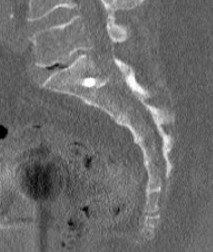

Check screw position with CT

- SI screw malposition in 2.6% cases using inlet / outlet views

- SI screw malposition in 0.1% cases using CT navigation